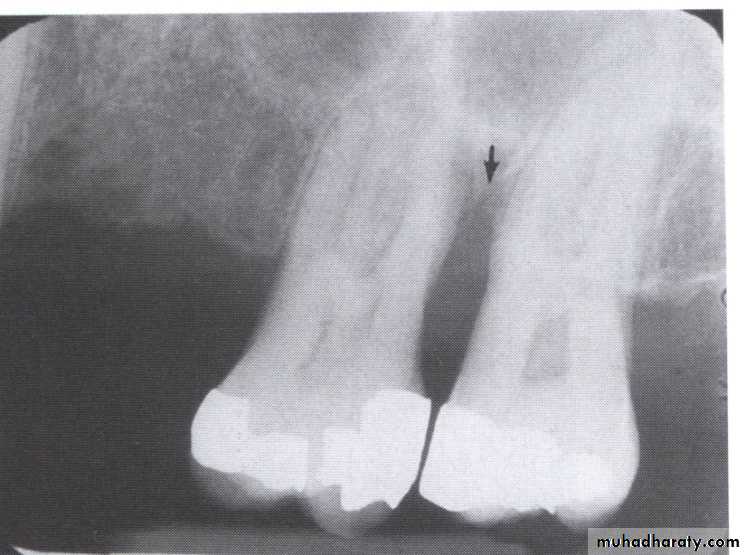

A-Calculus:

It is a stone-like concretion that forms on the crown & roots of the teeth due to the calcification of bacterial plaque.

Its appear as radiopaque on the dental radiograph.

its either pointed or irregular radiopaque projection extending from the proximal root surface.

Calculus may be seen as a ring-like radiopacity encircling the cervical portion of the tooth.